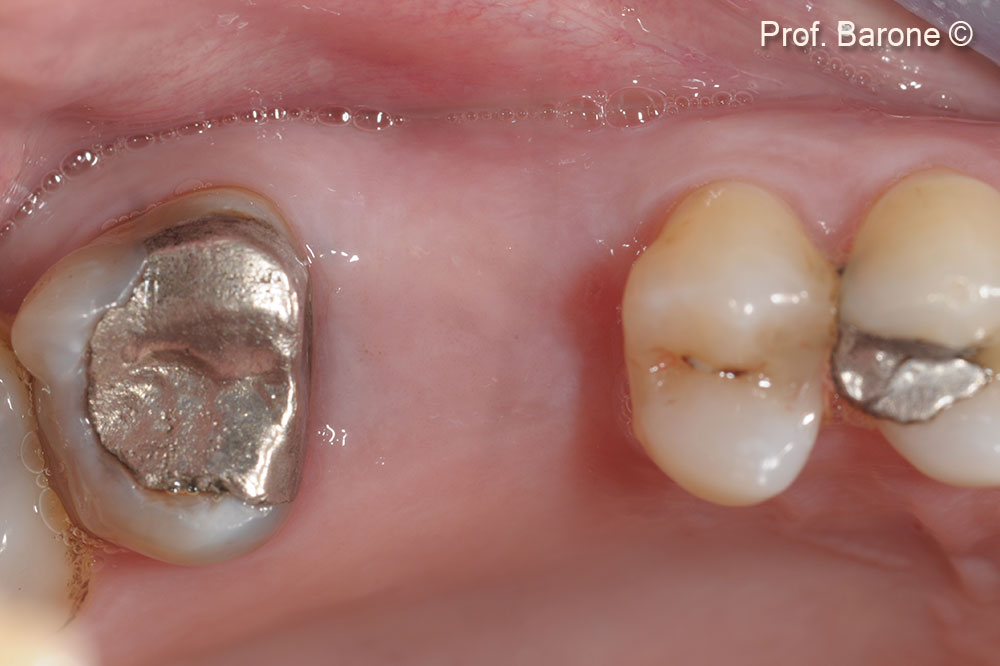

Một bệnh nhân nam (53 tuổi) cho thấy răng bị gãy.

Hình chiếu mặt nhai. Răng số 26